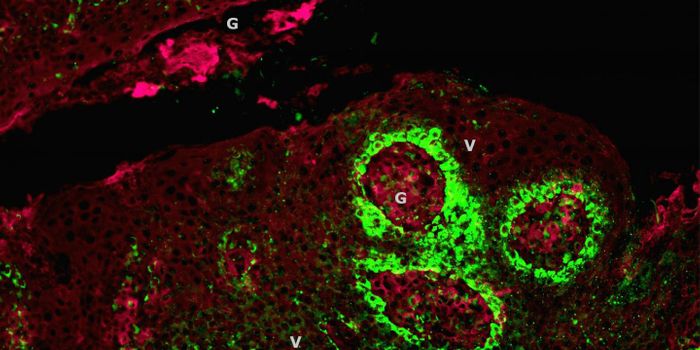

FEB 21, 2023Cell & Molecular BiologyThe Griffith Lab at UNC discovered telomeric protein & potential biomarker VR (green), shown in the nuclei (blue) of hum ...